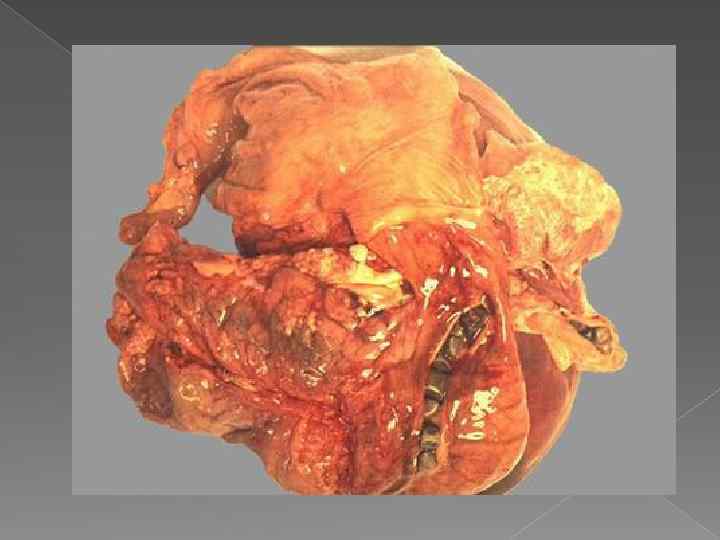

ОСЛОЖНЕНИЯ ХОЛЕЦИСТИТА Перфорация желчного пузыря

ОСЛОЖНЕНИЯ ХОЛЕЦИСТИТА Перфорация желчного пузыря